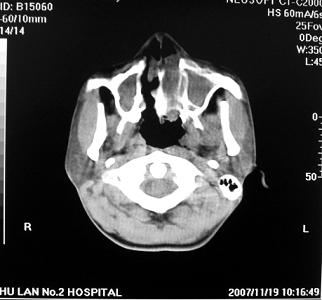

标题: CT10521:男。32岁,副鼻窦ct,请会诊。 [打印本页]

标题: CT10521:男。32岁,副鼻窦ct,请会诊。

男。32岁,鼻塞,流涕一年余。

考虑鼻腔内翻性乳头状瘤,筛窦、上颌窦炎症。建议进一步检查。

炎性病变.息肉阻塞副鼻窦口导致窦腔内潴留.

软组织密度影填满上颌蚪 筛窦及鼻腔,并导致筛骨 上颌窦内侧壁明显骨质破坏。多考虑:内翻性乳头状瘤!

双侧鼻腔内低密度软组织影,骨壁无明显破坏,鼻腔无扩大,双侧上颌窦、筛窦软组织影,窦壁增厚,结合临床考虑鼻息肉合并慢性上颌窦炎。